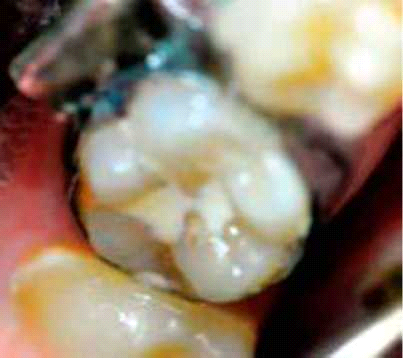

מחלת העששת היא מחלה חיידקית, כרונית, המועברת מדור לדור בצורה אנכית ובין בני אותו דור בצורה אופקית. המחלה היא בעלת נפיצות של מעל 90% באוכלוסייה המערבית ופוגעת בעיקר בחומר השן הקשה. בשנות ה-70 וה-80 של המאה הקודמת זוהתה ירידה בשכיחות המחלה בארצות מתפתחות בקבוצת הילדים והמתבגרים הצעירים[1], אולם מאז, הירידה בשכיחות המחלה נבלמה ובחלק מהמדינות נצפתה עלייה בשכיחות המחלה[2]. בילדי גיל בית ספר יסודי, רוב מוקדי העששת החדשים, עד 90% מהם, מופיעים בחריצים וחרירים של טוחנות קבועות[3]. ההגנה הראשונית באזור חרירים וחריצים היא על ידי שימוש בחומרים המונעים את התפתחות הנגע העששתי באזורים אלה. מבנה החריצים המרכזיים כטוחנות, כאשר הוא עמוק וצר (תמונה מס׳ 1), אינו מאפשר חדירה של סיבי מברשת השיניים לתחתיתו ומעודד פעילות עששתית.

אחת הבעיות במחקרים שבדקו אחיזה היא שההצלחה נקבעת קלינית בלבד ללא בדיקה רנטגנית. קיימים מקרים בהם פינה של האיטום נשברת במהלך השנים ומתחת מתחיל תהליך עששתי נרחב (תמונה 6).